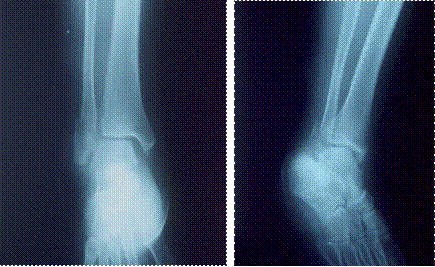

図3 受傷日翌日の受傷部レントゲン写真

左 正面像 腓骨遠位端部の転位が残存する

右 斜位像 初診時と同様の転位がみられる